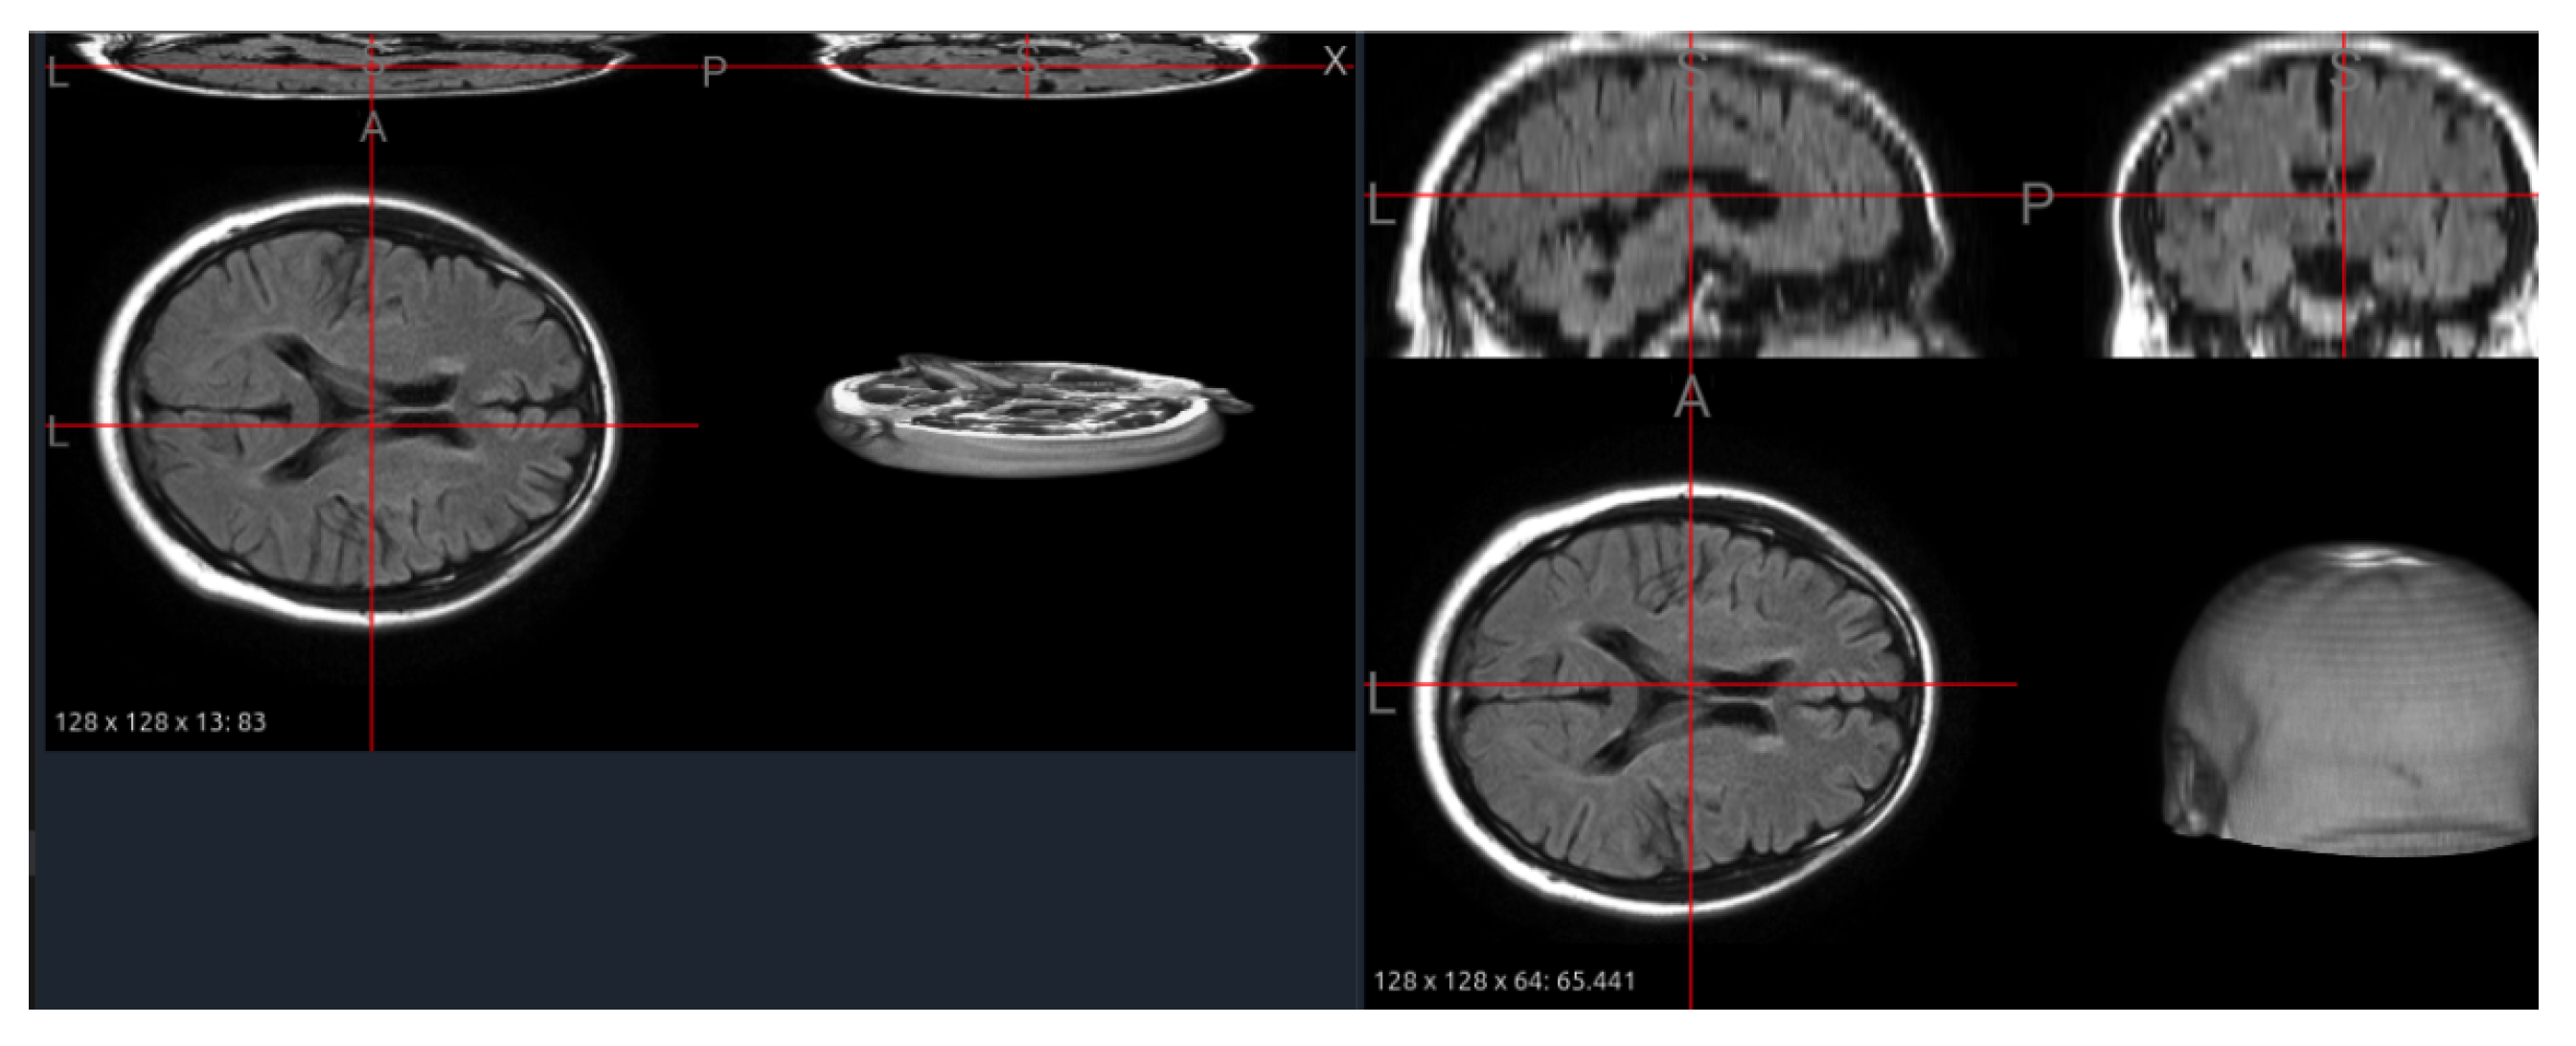

6.5. Interpolation of Thin-Slice Volumes

Several clinical datasets, such as MS-60, contain scans with limited z-axis coverage or thick slices, producing anisotropic volumes that hinder 3D convolutional learning. To mitigate this, we applied an automated interpolation procedure that increases through-plane resolution while maintaining anatomical scale. This step is not simply geometric resampling—it directly determines how well small, low-contrast lesions are represented in 3D feature space.

Figure 11 illustrates a FLAIR image from the MS-60 dataset before and after interpolation. The original scan (13 slices) shows severe discontinuities and collapsed tissue boundaries, whereas the interpolated version (64 slices) restores smoother cortical contours and continuous sulcal structures without distorting global shape. Quantitatively, the effective slice thickness decreased by approximately 4.8×, enabling isotropic patch extraction for pretraining and consistent input dimensions across datasets.

From a foundation model perspective, interpolation functions as a structural equalizer: it harmonizes volumetric resolution across sources, improving patch uniformity and kernel receptive fields. However, it also generates synthetic voxels that may obscure very small hyperintensities or produce interpolation artifacts along lesion edges. Thus, interpolation should be applied selectively—preferably on high-anisotropy datasets or in conjunction with uncertainty-aware augmentations—to balance geometric consistency and lesion fidelity.